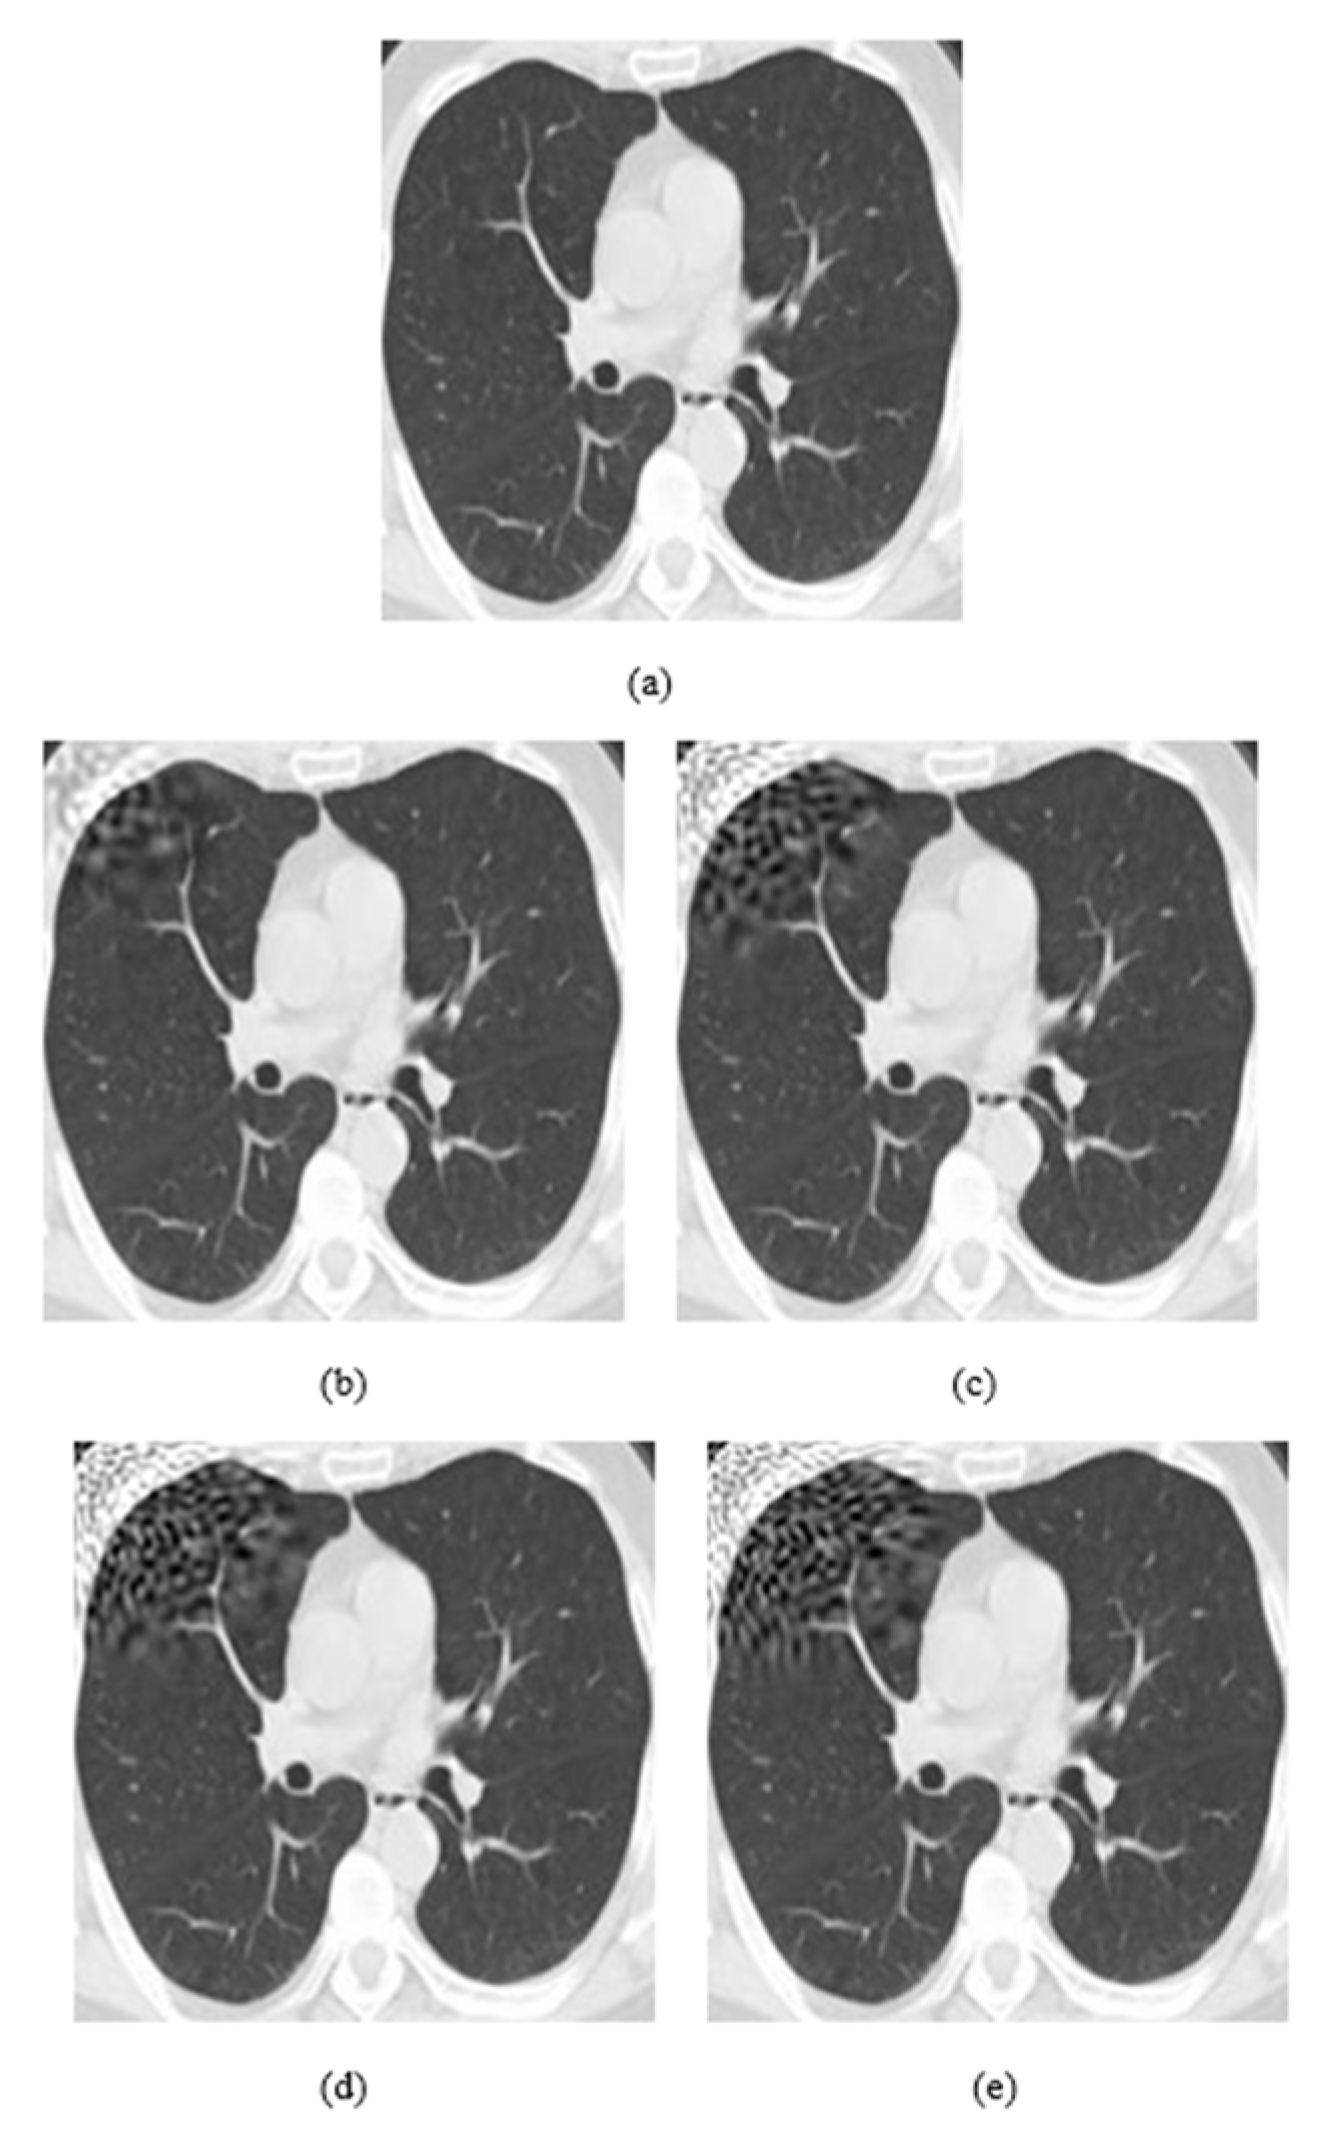

4.1. Datasets